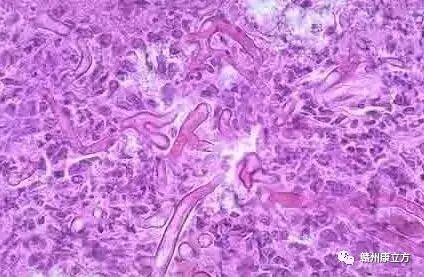

霉菌性阴道炎大多是由白色念珠菌(学名假丝酵母菌)感染引起的,因此霉菌性阴道炎也称为念珠菌性阴道炎,白色念珠菌作为常见菌群,它们在人体的皮肤、黏膜、消化道等多外都有寄生,但并不发病影响生活及工作,但是当遇到潮湿、闷热等适宜的环境时,念珠菌会大量繁殖侵袭人体,导致疾病的发生。所以在闷热的梅雨季节,很多女性都不约而同地发现,下身变得灼热瘙痒,甚至坐卧不宁,无法入睡,有时还尿频、尿痛,既痛苦又难堪——皆因她们的阴道在不知不觉间“发霉”了,即患上了俗称的霉菌性阴道炎。